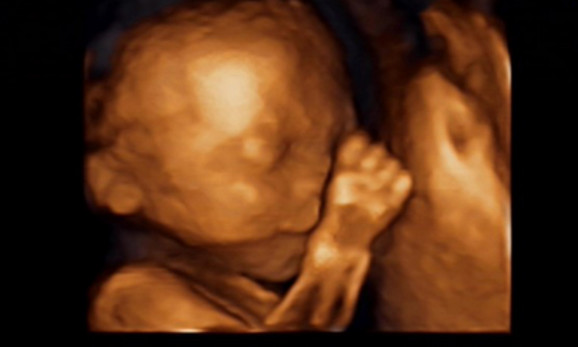

27岁的曹女士,已经怀孕六个月了。三天前,“孕味十足”的她,在丈夫的陪同下来到医院,准备进行提前预约好的四维彩超检查。但是万万没想到,检查结果让她的心情一下跌入低谷!通过影像显示,胎儿嘴唇中间竟然有一指宽的裂痕。经过医生再次仔细确认,腹中的胎儿确实患有唇腭裂,也就是“兔唇儿”。

唇腭裂患儿,是由于牙槽突间骨组织的缺失,造成上颌牙弓的完整性丧失,鼻基底部塌陷,牙槽突裂隙部恒尖牙萌出受阻。胎儿出生以后,需要通过牙槽突植骨术来完成唇部整形。手术具体怎么做,什么时候做,要做几次,这些都要根据孩子的具体病情。至于是否要生出来,这个就要由孕妇及家人自己决定。